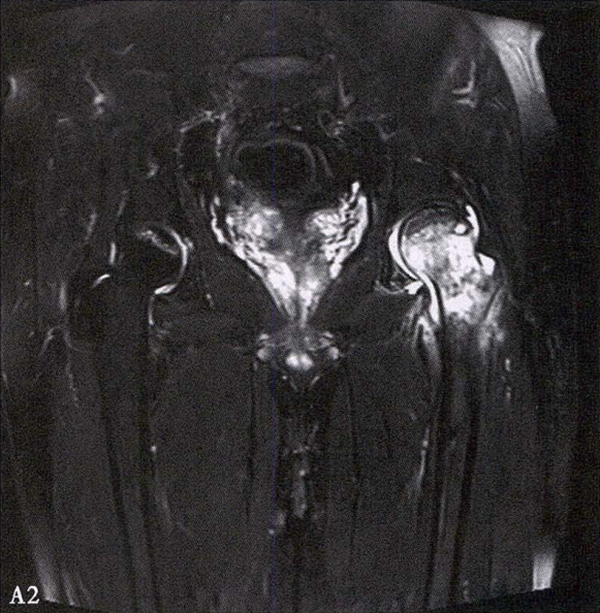

A.男性,71岁,双侧股骨头坏死,右侧Ⅰ期、左侧Ⅲ期。X线片示双侧股骨头形态可,右股骨头未见明显密度改变,左股骨头关节面下见局限性骨密度减低及增高区(A1)。MRI(T2加权像)示右股骨头内双线征,左侧不规则形混杂信号,坏死区远端骨髓水肿(A2、A3)。

B.男性,31岁,双侧股骨头坏死,双侧均为Ⅲ期。X线片示双侧股骨头密度不均、股骨头稍变扁(B1)。MRI(T1加权像)示股骨头内多发不规则信号带(B2),股骨头内凸向大转子的双线征(白色箭)和软骨下骨骨折(白色三角)。